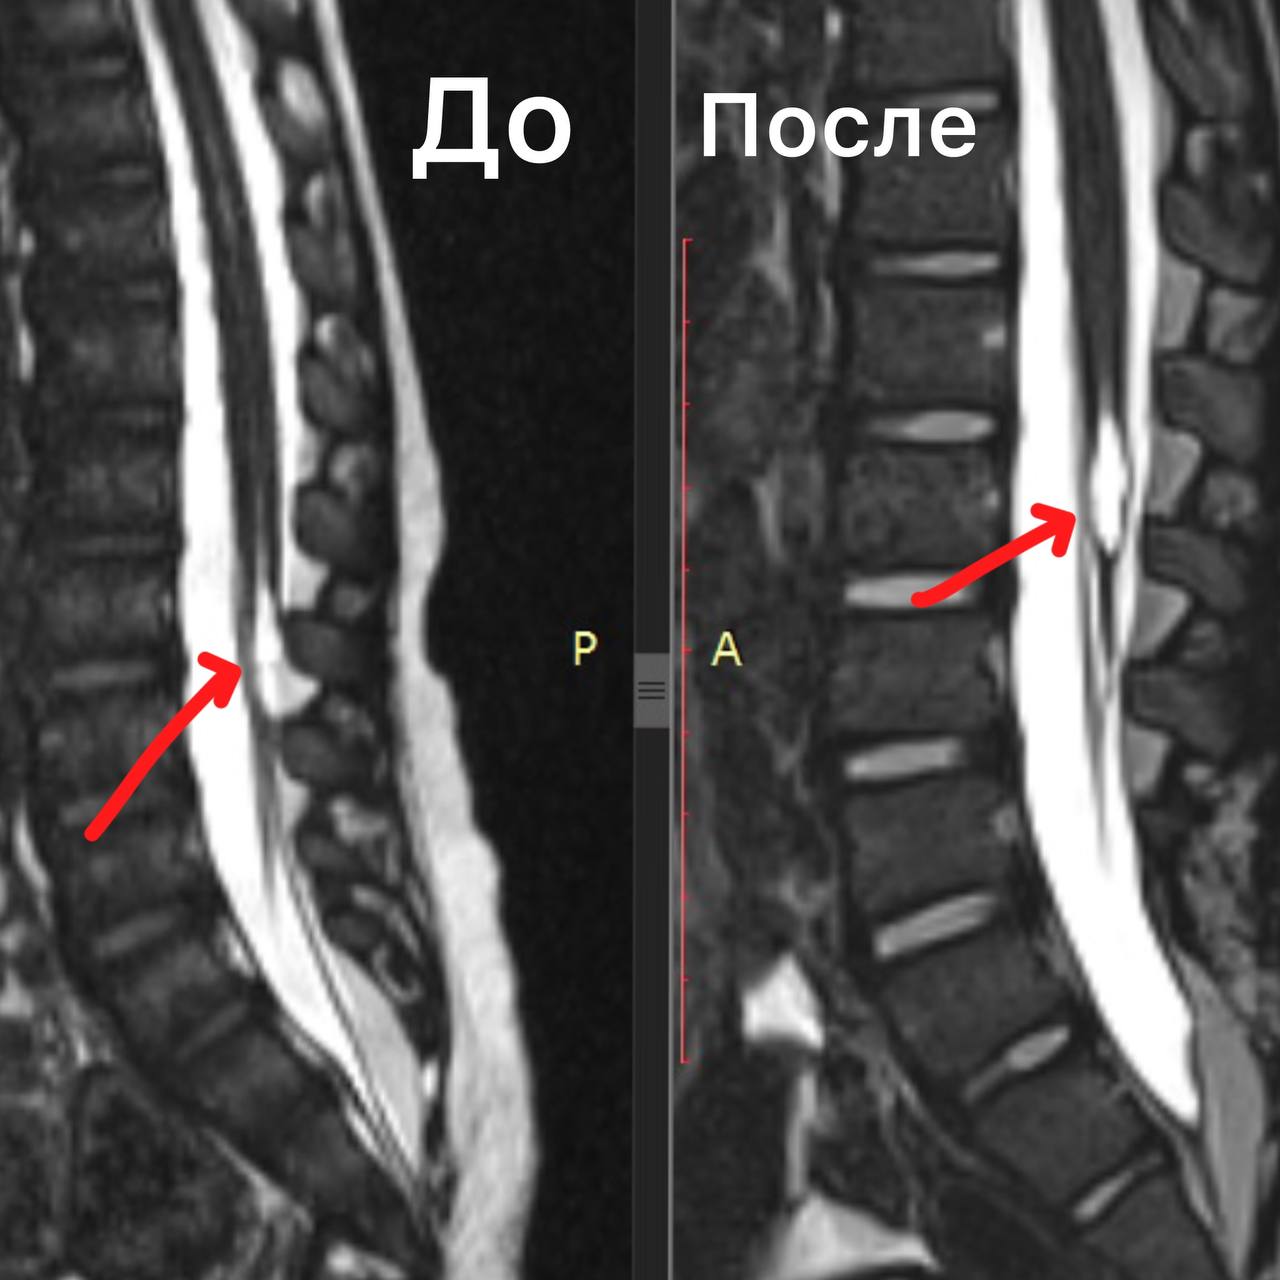

Естественное течение аномалий развития спинного мозга с известным неблагоприятным безоперационным прогнозом в настоящее время встречается редко, поскольку в большинстве случаев хирургическое лечение проводится в раннем возрасте, а длительное наблюдение за такими пациентами в целом считается неэтичным, за исключением единичных случаев и некоторых форм порока. Тем более ценно данное клиническое наблюдение.

При рождении у ребенка выявлено подкожное образование в поясничной области, девочка наблюдалась по месту жительства у детского хирурга, невролога, ортопеда, до года осмотрена нейрохирургом, выявлен легкий нижний вялый парез (мышечная слабость) справа. По данным МРТ диагностирован порок развития - липомиеломенингоцеле, фиксированный спинной мозг.

В дальнейшем наблюдалась ортопедом с диагнозом сколиоз I-ІІ ст., в возрасте 5 лет впервые выявлено нарушение функции тазовых органов - гиперрефлекторный мочевой пузырь, с возраста 13 лет отмечено укорочение правой нижней конечности до 1см, болевой синдром, периодическое (стрессовое) недержание мочи.

В динамике формирование походки с анталгической установкой, прихрамывание, степпинг, при осмотре неврологом ахилловы рефлексы отсутствуют, сила в ногах снижена до 3 баллов дистально, поверхностная чувствительность снижена до анестезии по типу низких носков с двух сторон, паралитическая эквино-варусная деформация обеих стоп.

К возрасту 17 лет выраженные боли в спине и ногах (больше в правой), укорочение правой нижней конечности на 2 см, гипотрофия мышц правого бедра и правой голени - минус 2см, разгибательная контрактура обоих голеностопных суставов и левого коленного сустава2 ст., частые мочеиспускания, периодическое дневное недержание мочи, слабость в ногах, выраженное нарушение походки.

Причина столь длительного течения заболевания в данном случае заключается, со слов мамы ребенка, в опасениях, вызванных как неубедительными доводами в пользу операции со стороны специалистов по месту жительства, так и ложными страхами, внушаемыми, со стороны родителей других пациентов (зачастую с абсолютно другими диагнозами) из «родительских чатов»: не будет ходить, станут «резать» каждый год и т.д.

Операция по освобождению спинного мозга из рубцовой и жировой ткани длилась 6 часов, цели вмешательства были достигнуты, девочка выписана на 7е сутки без ухудшения состояния и с надеждой на то, что удалось остановить прогрессирование заболевания. При этом очевидно, что в результате длительной фиксации и натяжения спинного мозга, большая часть проблем, в первую очередь ортопедических, к сожалению, уже не разрешится…